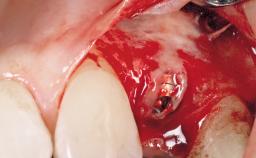

Surgical treatment of a 67-year-old male patient exhibiting an extended edentulous space in the anterior maxilla after the removal of three hopeless incisor teeth.

The video demonstrates implant placement using a surgical stent according to the principle of prosthodontically driven implant placement. The deficient ridge is augmented with locally harvested autologous bone chips, a superficial layer of xenogenic DBBM particles and a resorbable collagen membrane. The surgery is completed with a precise, tension-free primary wound closure.

Bone Augmentation Horizontal|Simultaneous

Augmentation Materials Autogenous chips|Xenogenous|Membrane

Bone Volume Deficient horizontally, allowing simultaneous augumentation